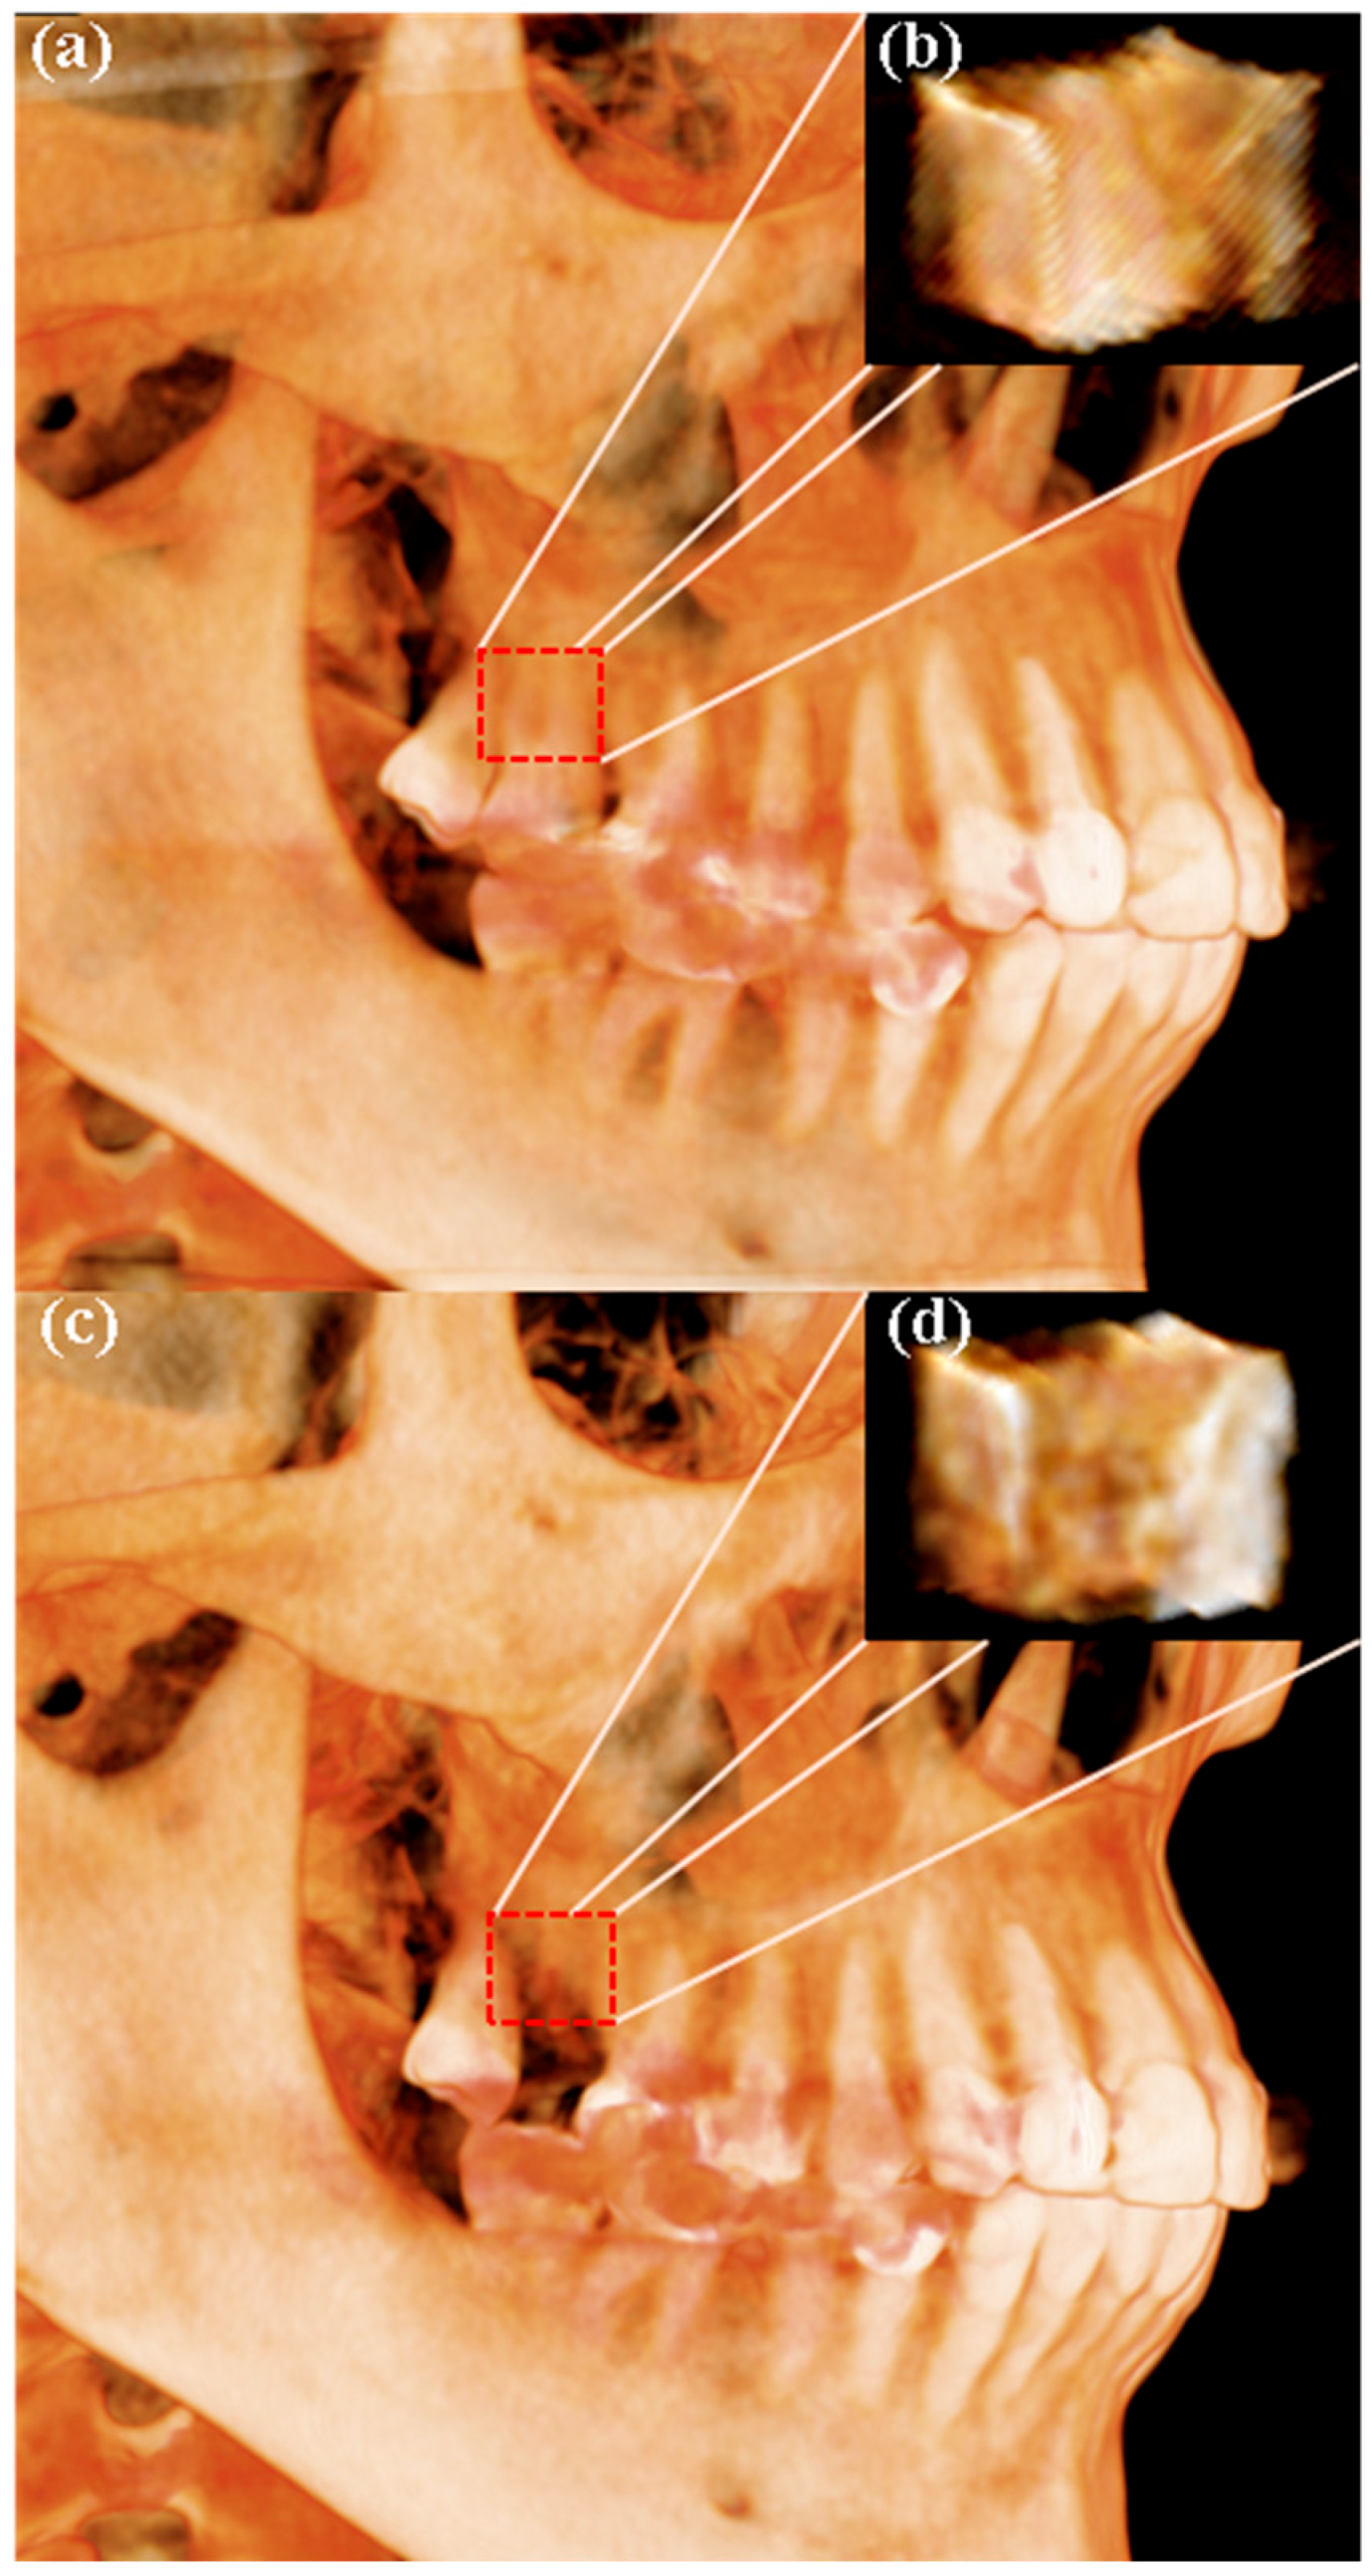

2.7. Radiographic Analysis Using CBCT

3.3. Results of Radiographic Analysis

4. Discussion